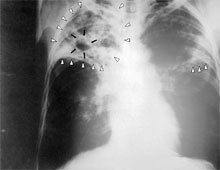

Флюрограма легенів людини хворої на туберкульоз.

(phil.cdc.gov)